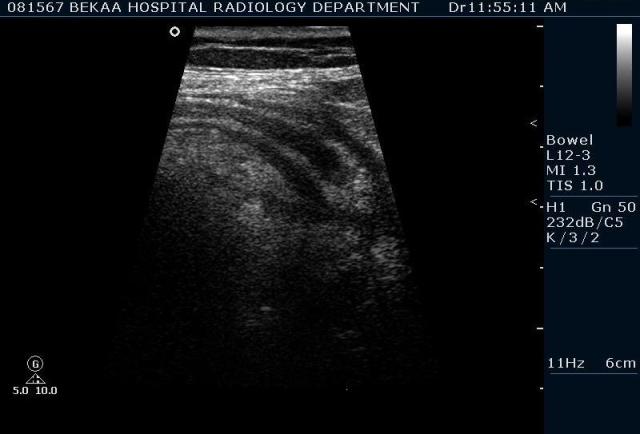

Диагностика острого аппендицита по УЗИ: очень актуальная тема; УЗ аппараты практически есть во всех клиниках; метод доступный и не сложный; главное владеть правильной техникой. Не буду загружать лишней теорией и разными ссылками; поделюсь практическим опытом. У меня линейный датчик 3-12 мегагерц с плавающей частотой; аппарат Филипс HD 11, всегда включаю соно-КТ (9800 цифровых каналов) и гармонику когда смотрю кишечник. Нормальный аппендикс видеть можно; но вопрос зачем??? Как правило, если при наличии достаточного опыта аппендикс не виден; значит скорей всего аппендицита нет. Когда "идешь" на аппендицит то главное по началу набраться терпения и......хорошая компрессия! По началу надо минут 10-15; потом когда появится достаточный опыт; за 2-5 минут можно справится и получить отличную визуализацию. Мочевой пузырь лучше опорожнить; часто он приподнимают тонкий кишечник и может закрыть "окно" через которое будет видно апендикс. Сначала находим слепую кишку потом находим илео-цекальное соединение;

после начинаем производить хорошую компрессию датчиком попрося пациента сообщить в какой точке боль наиболее выражена; медленными движениями датчика сканируем область наибольших болевых ощущений и как правило находим утолщенный отросток. Лучше начинать с поперечной визуализации и идти к верхушке аппендикса что бы убедится что это аппендикс и он заканчивается, а не тонкая кишка (которая если и закончится то только переходя в слепую); потом надо аккуратно развернуть продольно датчик и посмотреть от верхушки аппендикса к слепой. Норма диаметра: 3-4 мм; 5-6 мм под вопросом (клиника решает; но я в катаральный аппендицит не верю); 7-8 мм и больше, не компремируемый (фиксированный отросток)-острый аппендицит! Помимо наличие утолщенного аппендикса; признака "бычьего глаза" (bull-eye sign) при поперечном сканировании; надо обращать внимание на присуствие аппендоколитов в просвете; деструкцию стенки и свободной жидкости в зоне интереса.